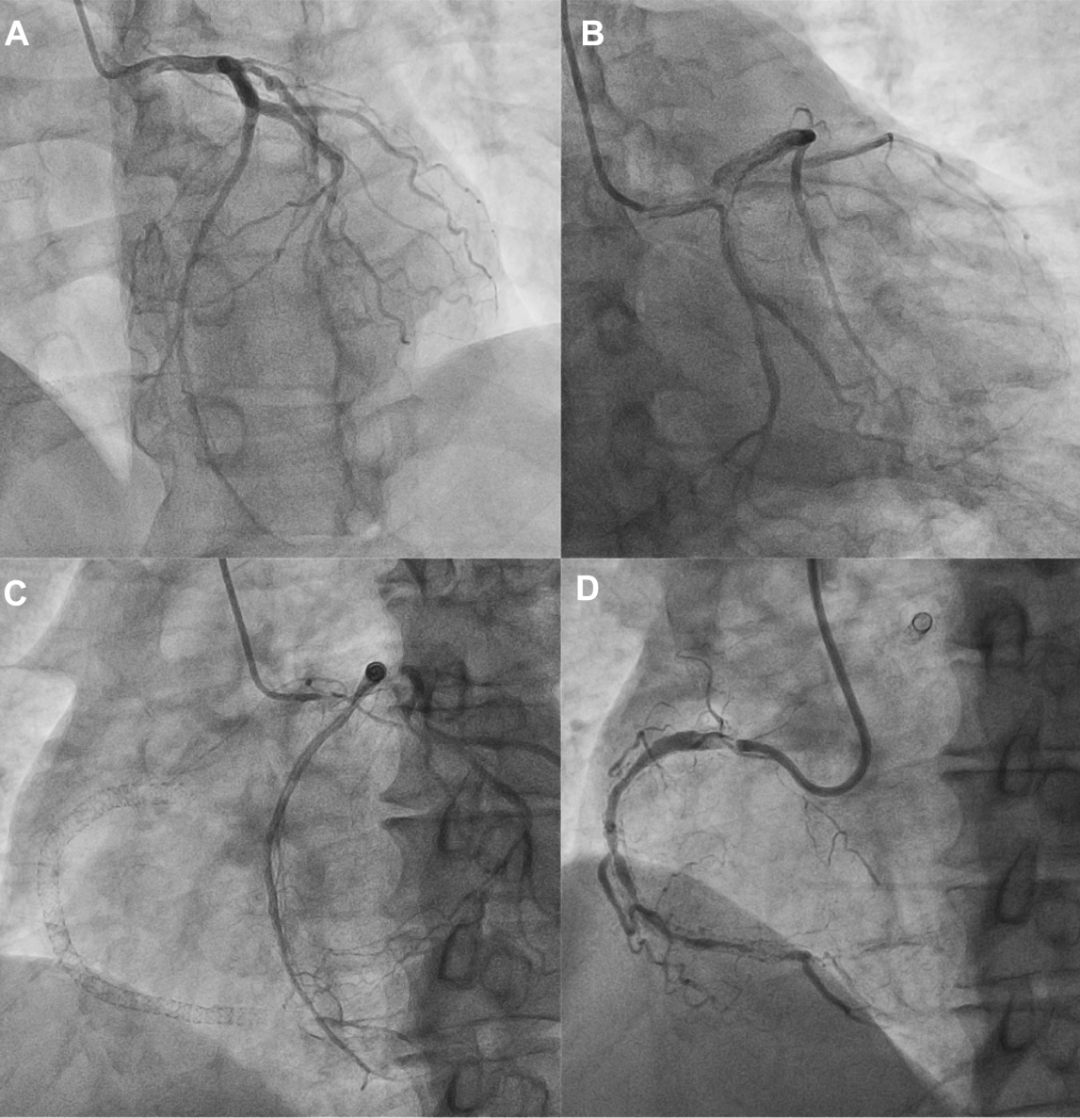

冠状动脉造影结果显示,LAD和回旋支(LCX)无明显狭窄;RCA中段存在弥漫性支架内再狭窄,远端呈CTO改变;LCX向远端RCA提供了良好的心外膜侧支循环(图1)。

图1 冠状动脉造影结果

冠脉造影显示(A和B)LAD、LCX无明显狭窄,LCX远端有心外膜侧支血管供应RCA远端;(C)LCX远端有发育良好的心外膜侧支血管供应RCA远端;(D)RCA中远端弥漫性支架内再狭窄,且RCA远端为CTO。